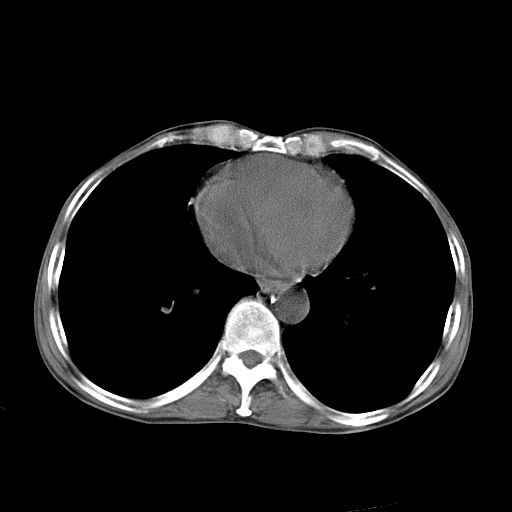

以下是引用苯小孩在2007-5-24 12:47:00的发言:[br]右侧肺门处不均匀密度软组织块影,远端肺组织见斑片模糊影,纵隔内淋巴结明显肿大,边界不清.<纵隔窗第12层面支气管内似见软组织结节>[br]考虑:1、右侧中央性肺癌并阻塞性肺炎并纵隔淋巴结转移可能性大.建议强化或纤支镜进一步检查.[br]2、隆突下淋巴结肿大/食道病变?请做鉴别检查.

以下是引用jw-830在2007-5-24 15:24:00的发言:[br][br] [br] 考虑右肺中央型肺癌并阻塞性炎症,右肺门及纵隔淋巴结转移。 [br] [br][br]